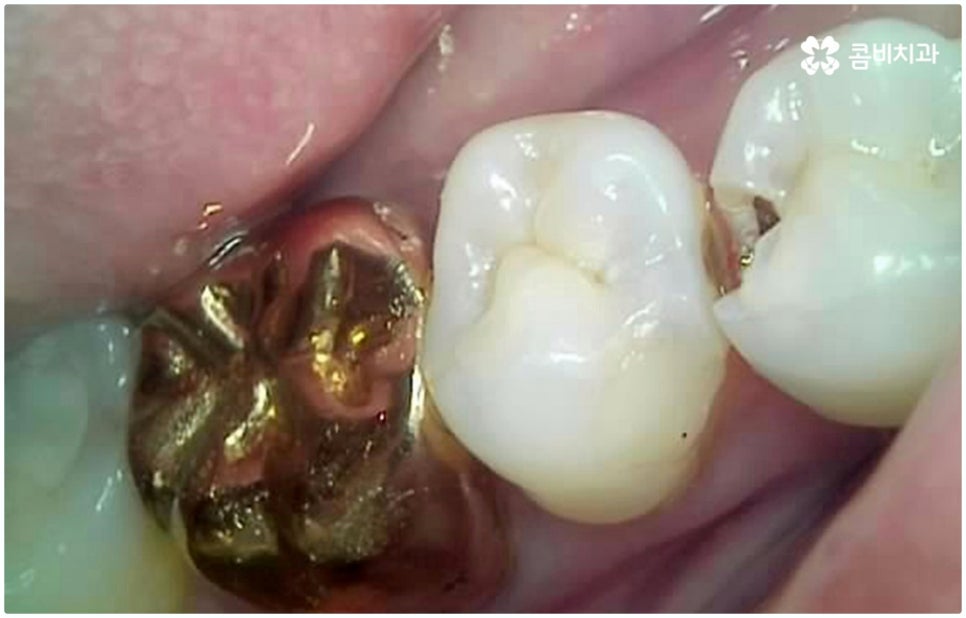

예를 들어 충치가 악화되어 세균이 치아 내부 치수 조직까지 침투한 경우 감염된 신경을 깨끗하게 제거하고 신경관 내부를 생체친화 충전재로 밀봉한 후 크라운으로 덮어 씌워주는 신경치료를 하게 되는데, 이때 감염 부위가 제대로 제거되지 않거나 2차 감염이 일어나 손상이 치아 뿌리까지 진행되면 자연 치아를 살리는 게 어려워 질 수 있습니다. 시기를 놓치면 재신경치료, 치근단 절제술 등의 보존 치료 역시 소용이 없어질 수 있으니 만약 신경 치료를 받은 치아가 있다면 더욱 신경써서 위생 관리에 주의하시고 검진을 통한 관리를 게을리 하지 않으시길 권유드리고 있어요.

물론 타고난 치아만큼 편안하게 사용하기는 어려우므로 치아 상실에 이르기 전에 자연 치아를 살리는 방향으로 보존 치료를 해 주는 게 구강 건강을 유지하는데 보다 바람직한 방법이라고 할 수 있는데요. 하지만 이미 해당 치아가 치아로서의 기능을 상실했다면 발치하지 않고 그대로 둔다는 것이 더이상 의미가 없으며 오히려 시간이 지날수록 주변 치아나 잇몸까지 손상이 번질 수 있으니 상황에 따라 늦지 않게 올바른 대처를 해 줄 필요가 있어요